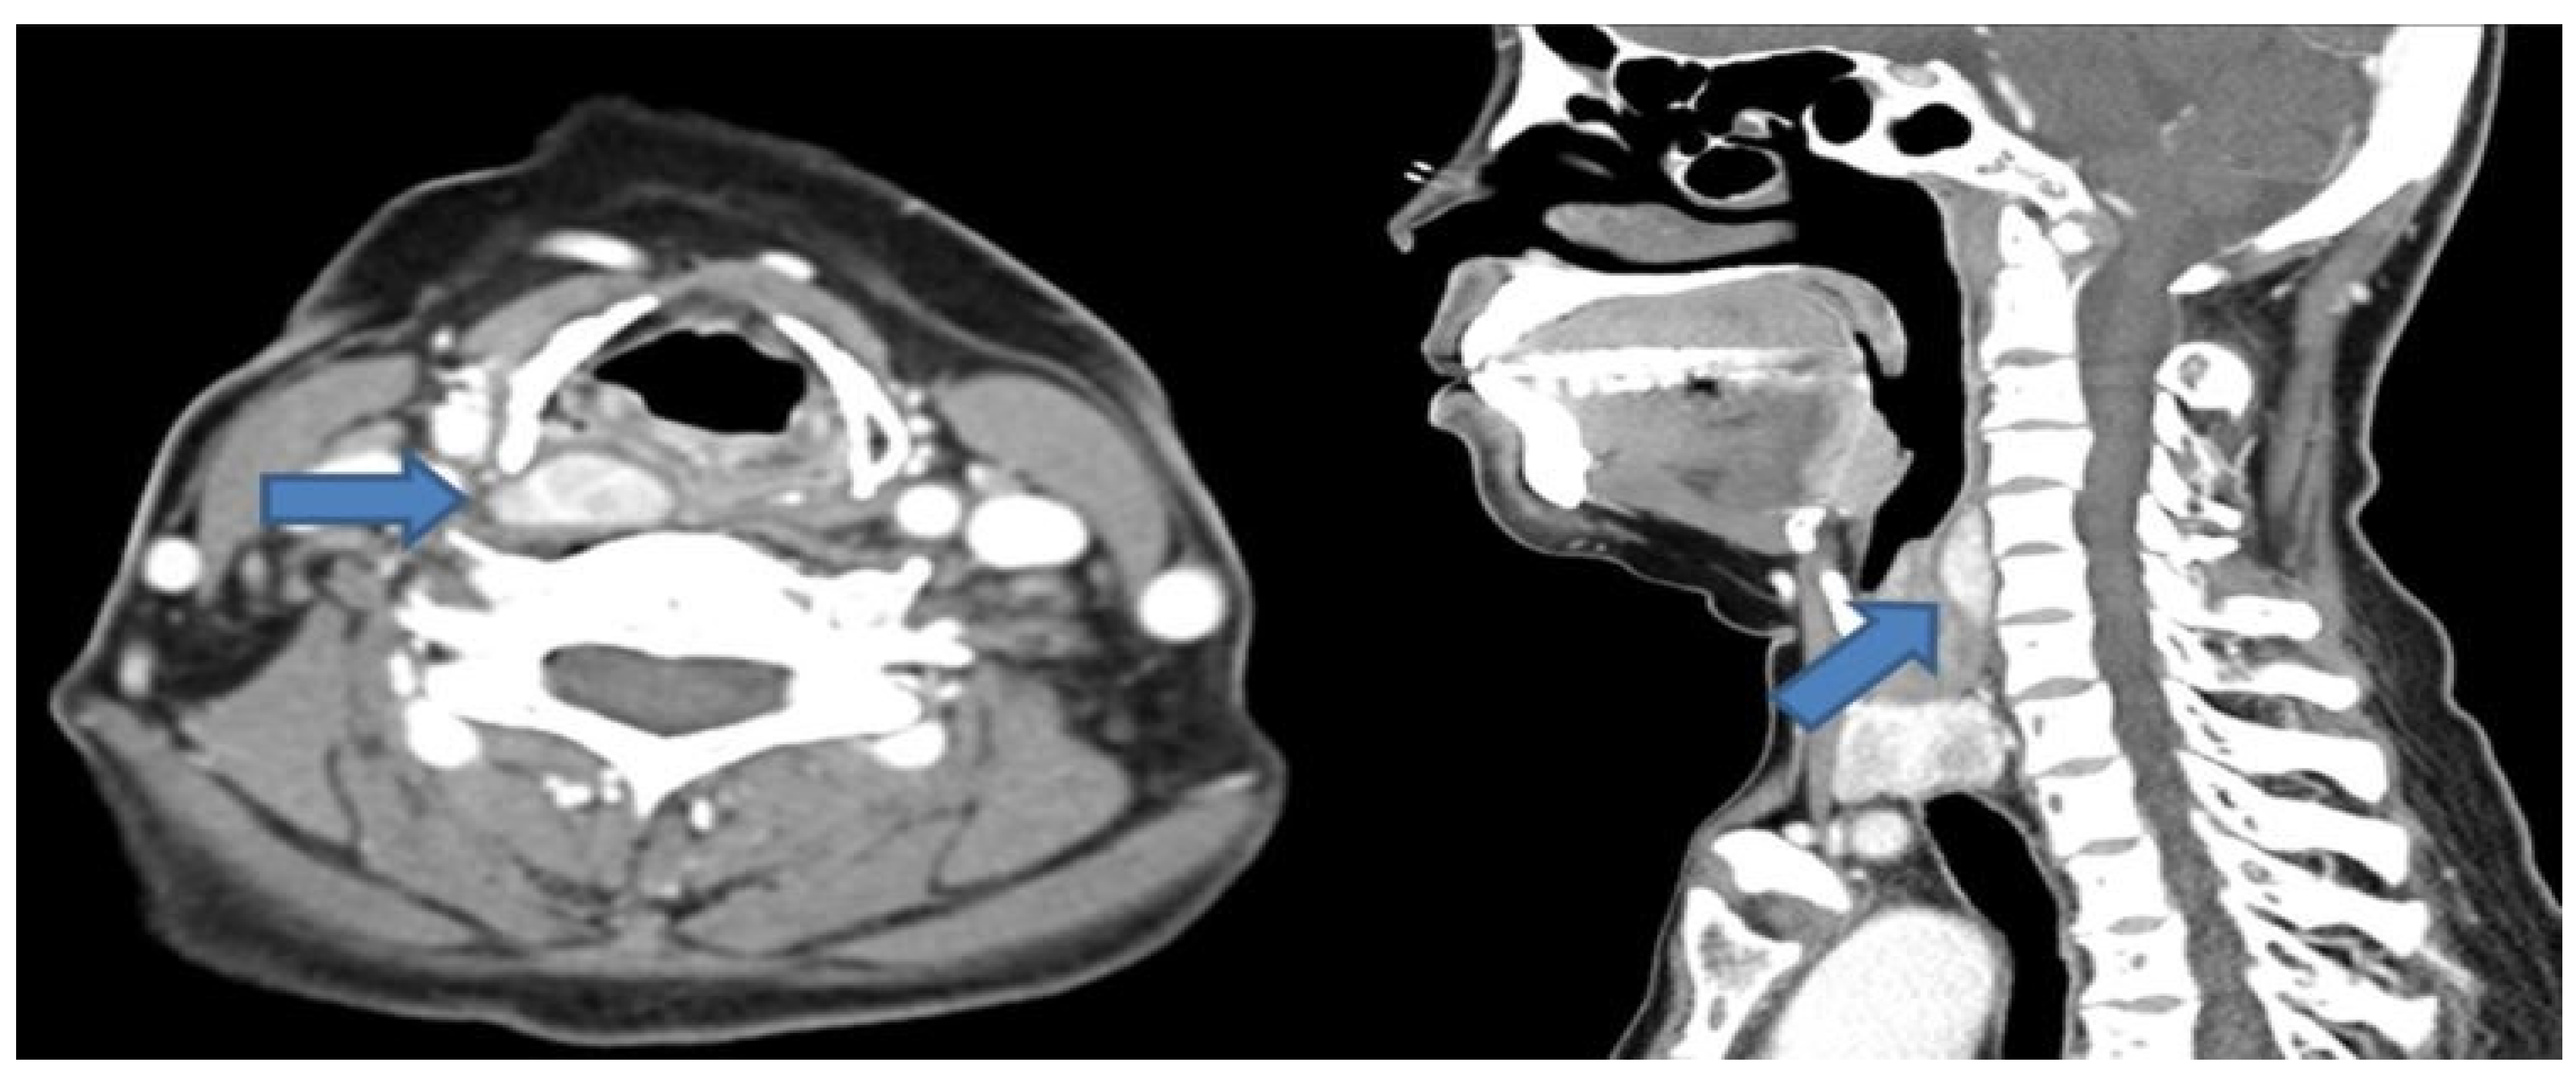

A 51-year-old female patient with end-stage renal disease on dialysis was referred by the nephrology department due to suspected osteoporosis and the presence of osteoblastic lesions. Laboratory results indicated elevated serum calcium (10.4 mg/dL; normal range: 8.4~10.2 mg/dL), intact parathyroid hormone level (383 pg/mL; normal range: 12.0~65.0 pg/mL), and low serum phosphate (1.71 mg/dL; normal range: 2.3~4.7 mg/dL), as well as 25-OH vitamin D (13.6 ng/mL; normal range: 20.1~100 ng/mL). Subsequent cervical computed tomography (CT) scans displayed a well-defined enhancing mass measuring about 2.6cm in the retropharyngeal space at the upper level of the right thyroid cartilage. Based on clinical symptoms and radiological findings, additional parathyroid imaging was performed to precisely locate the suspected parathyroid adenoma. The parathyroid scan showed the presence of an upper right parathyroid adenoma in the retropharyngeal region, prompting the patient to seek surgical consultation (Figure 1). A transverse incision of approximately 5 cm was made slightly to the right of the midline of the neck, exposing the sternocleidomastoid (SCM) muscle. Following the lateral retraction of the SCM muscle, the right thyroid gland was discerned, and an incision was performed to reach the retropharyngeal space at the hyoid bone level. Enlarged lymph nodes were observed in the adjacent region, and by gently displacing the thyroid to the left, the parathyroid mass situated in the retropharyngeal space was revealed. Careful dissection was carried out to separate the retropharyngeal mass from the surrounding tissues. A portion of the excised mass was subjected to frozen section analysis, confirming its parathyroid origin. Intraoperative intact parathyroid hormone (iPTH) levels were measured and revealed a gradual reduction after the removal of the mass. The iPTH levels decreased to within the normal range as seen via serum testing 20 min after tumor removal. Lobectomy was performed through conventional techniques without injury to the recurrent laryngeal nerve and inferior parathyroid gland. No postoperative complications were observed, and the patient was discharged on the 5th day post-surgery. Subsequent pathology results of the thyroid nodule confirmed papillary thyroid cancer with no extrathyroidal extension or neural involvement and the retropharyngeal mass was diagnosed as a parathyroid adenoma (Figure 2). After the surgery, the patient’s blood tests showed that serum calcium (8.61 mg/dL), parathyroid hormone (32 pg/mL), and serum phosphate (4.57 mg/dL) levels had all returned to within the normal range. Ultimately, significant clinical improvement was achieved, and the patient is now under regular observation and follow-up (Figure 3).

Figure 1. Preoperative enhanced neck CT shows an approximately 2.6 cm well-defined mass in the right retropharyngeal space (axial view, left blue arrow). The suspicious lesion in the retropharynx is located at the level of the upper thyroid cartilage (sagittal view, right blue arrow).